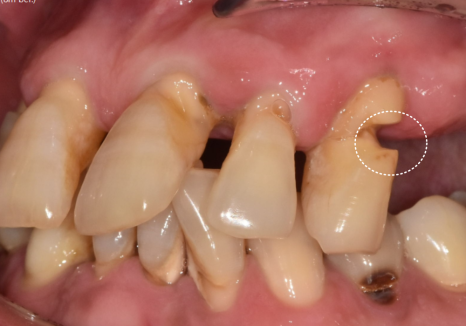

특히, 틀니 고리가 걸리는 치아들에

너무 많은 힘이 쏠리다 보니,

250531

뿌리 쪽이 심하게 패어

몹시 약해진 상태였습니다.

이렇게 되면 틀니를 아무리 새로 맞춰도

잇몸만 아프고 제대로 씹기가 참 힘듭니다.